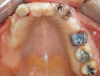

Fig 1. Initial occlusal view of maxillary arch.

Figure 1